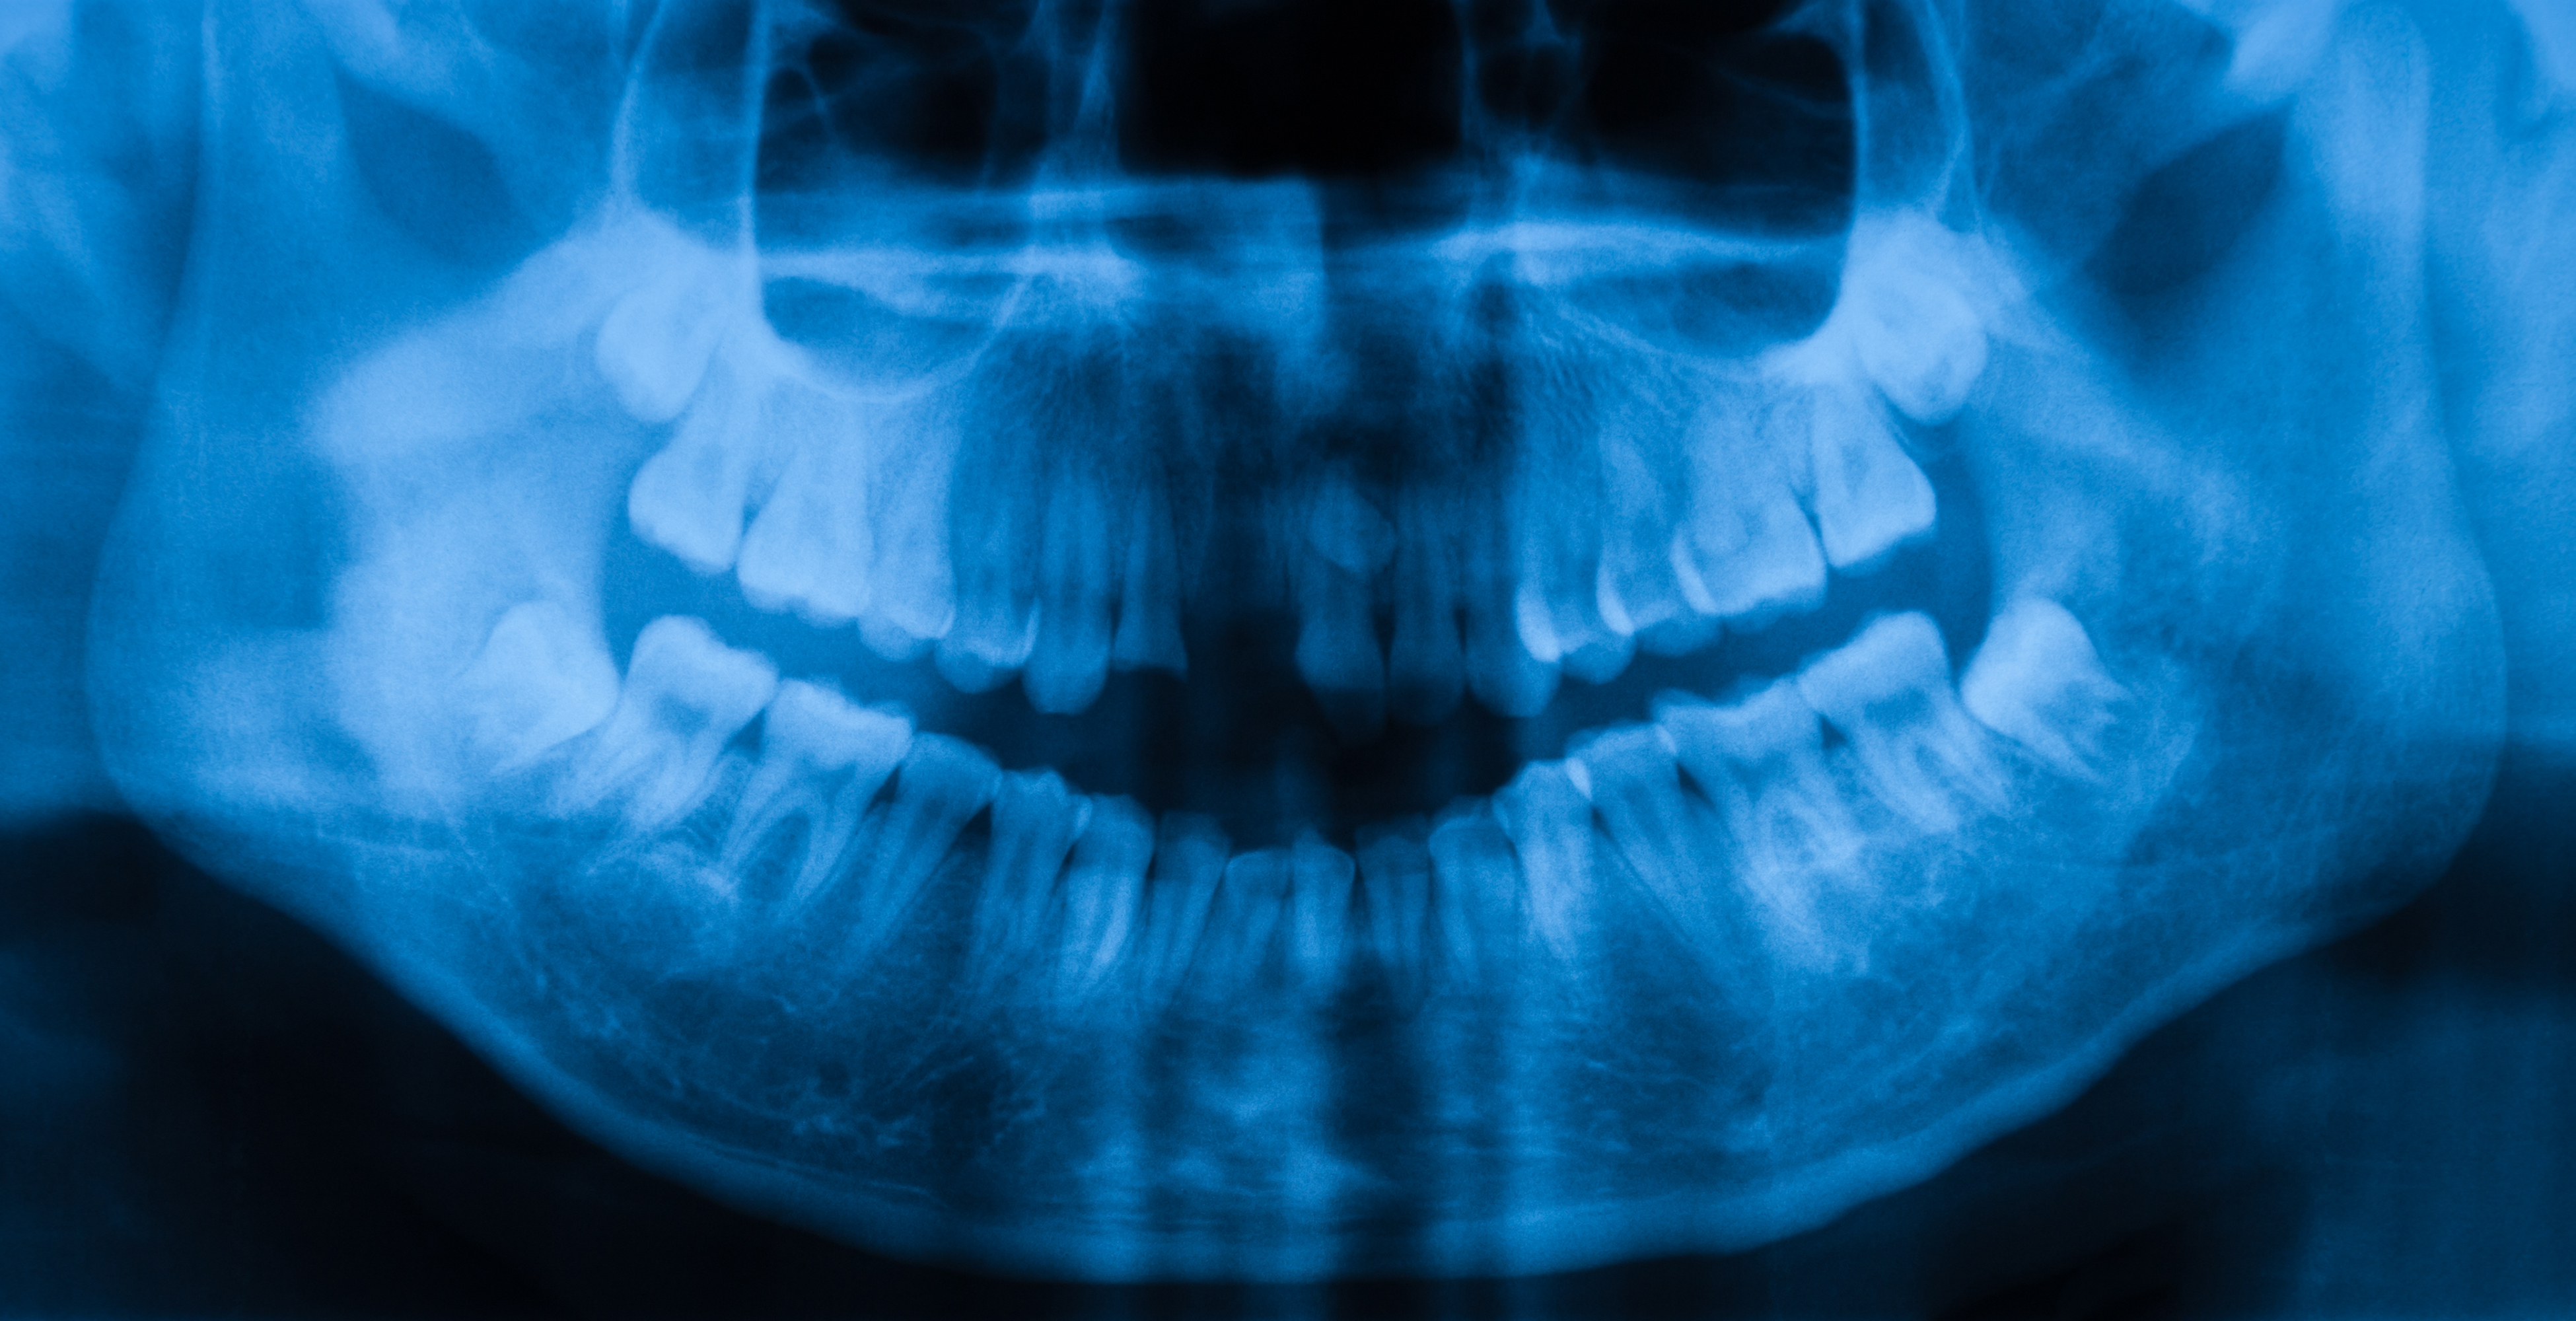

While wisdom teeth are a leftover oddity from our days as a stick-gathering, reed-chewing people who needed back-ups for their teeth, today, they continue to pose unexpected problems. Namely, they lead to post-surgical pain for which many dentists prescribe highly addictive opioids.

Not to mention the fact that, because of their tendency to cause painful swelling and impacted teeth, wisdom teeth removal is a very common procedure. Around 85% of wisdom teeth are eventually removed, according to the American Association of Oral and Maxillofacial Surgeons.